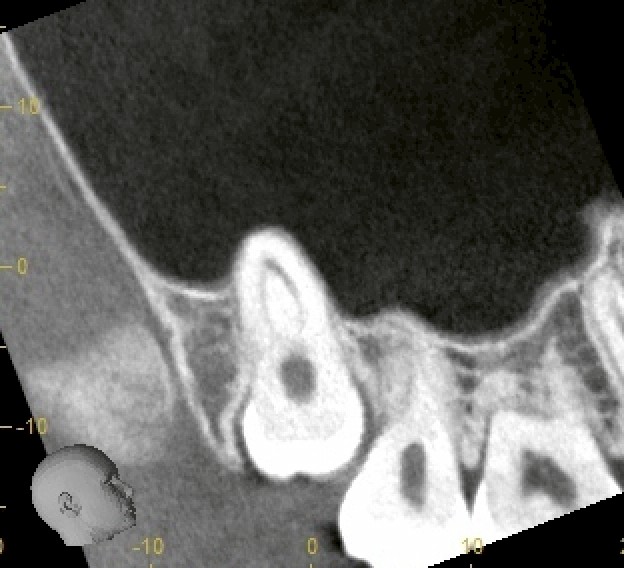

レントゲン・CTを確認すると、親知らずは深い位置で埋伏しており、歯根の一部が上顎洞に入り込んでいる可能性がありました。

今回のケースでは、CT画像で位置を正確に把握し、愛護的に処置を行ったため、抜歯後に上顎洞との交通は認められませんでした。

今回のようにCTでの事前確認と、愛護的な抜歯操作を行うことで、安全に処置を完了することができます。